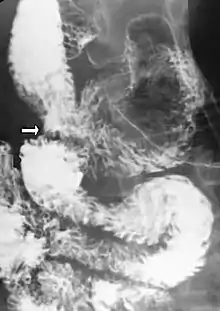

Diagnosis is very difficult, and usually one of exclusion. SMA syndrome is thus considered only after patients have undergone an extensive evaluation of their gastrointestinal tract including upper endoscopy, and evaluation for various malabsorptive, ulcerative and inflammatory intestinal conditions with a higher diagnostic frequency. Diagnosis may follow X-ray examination revealing duodenal dilation followed by abrupt constriction proximal to the overlying SMA, as well as a delay in transit of four to six hours through the gastroduodenal region. Standard diagnostic exams include abdominal and pelvic computed tomography (CT) scan with oral and IV contrast, upper gastrointestinal series (UGI), and, for equivocal cases, hypotonic duodenography. In addition, vascular imaging studies such as ultrasound and contrast angiography may be used to indicate increased bloodflow velocity through the SMA or a narrowed SMA angle.[14][15]

Upper gastrointestinal series showing extreme duodenal dilation (white arrow) abruptly preceding constriction by the SMA.- Ultrasound showing SMA syndrome[18]